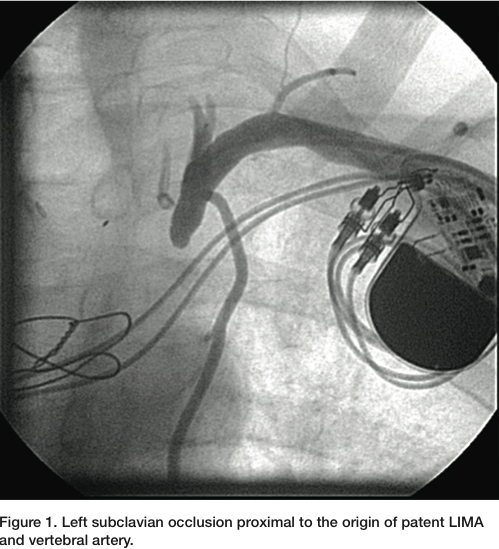

A 6 French (Fr) Glidesheath (Terumo) was inserted in the left radial artery. A Judkins right (JR) 4 catheter was advanced from the left radial over a J wire. The left subclavian angiogram showed a 100% chronic total occlusion (CTO) of the left SA proximal to LIMA origin (Figure 1). There was biphasic flow in the left vertebral artery, suggesting the left subclavian artery was filled by collaterals through the cerebral circulation. The LIMA was free of any disease and there was good LAD runoff (Figure 2). The right femoral artery was accessed with a 6 Fr